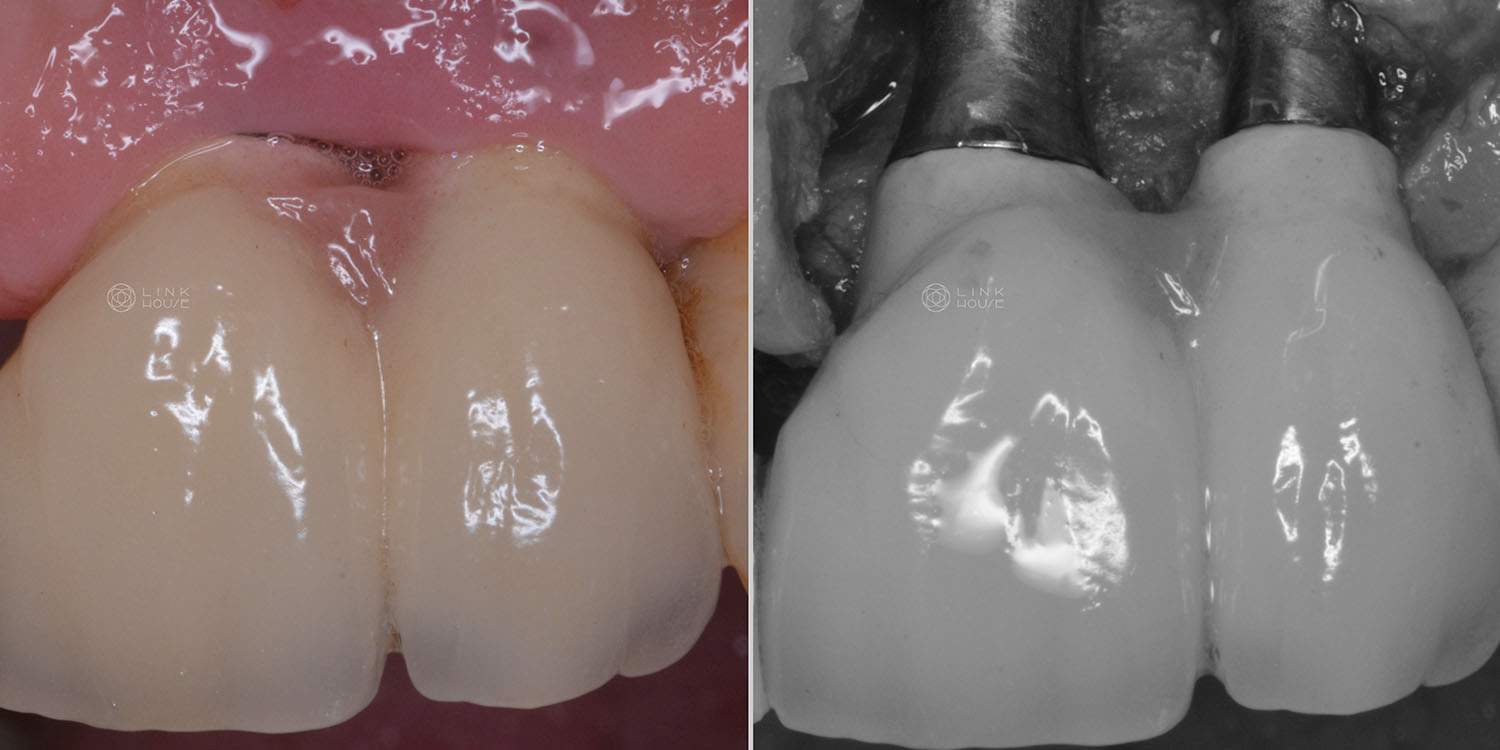

Gum Recession

Gum recession is when your gum tissue pulls away from your teeth, exposing the roots underneath.

It’s caused by several factors, including overzealous brushing, mouth trauma, periodontal disease, orthodontics, lip/tongue piercings and genetics.

Exposed teeth roots increase your risk of tooth decay, sensitivity and bone loss around teeth.

Gum surgery can improve thinning gums and gum recession. In some cases, a gum graft is required to cover the roots of the exposed teeth and add volume to your gums. This restores the missing gums and reduces the risk of further gum recession. Gum graft surgery can be performed on one tooth or multiple teeth.

There are many gum grafting techniques and materials available. We commonly take tissue from your palate (the roof of your mouth) and move it to the area of recession. In some cases, though, we may use a substitute grafting material.